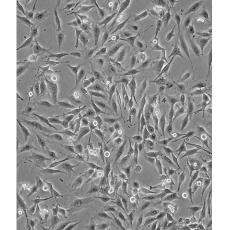

形態(tài)特征 spindle shaped

細(xì)胞描述 MDA-MB-435S是一種紡錘形的細(xì)胞,1976年由其親本(435)中篩選得到。435是從31歲的轉(zhuǎn)移性乳腺導(dǎo)管腺癌女性患者胸水中分離得到。當(dāng)用熒光染料對(duì)微管蛋白進(jìn)行染色時(shí)親本細(xì)胞顯現(xiàn)散布特征(II型)。最近通過cDNA陣列研究表明,親本(MDA-MB-435)可歸入黑素瘤起源。